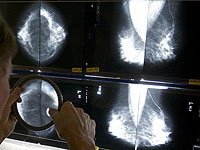

Исследование показало, что применение искусственного интеллекта при скрининге рака молочной железы связано со снижением на 12% числа случаев рака, выявляемых в последующие годы, а также с более высокой долей ранней диагностики. По словам ученых, это крупнейшее на сегодняшний день исследование, посвященное использованию ИИ в маммографическом скрининге. В нем приняли участие 100 000 женщин в Швеции, проходивших обследование с апреля 2021 по декабрь 2022 года. Участниц случайным образом разделили на две группы: в одной маммограммы анализировались с помощью системы ИИ, в другой снимки оценивали два рентгенолога по стандартной схеме.

Алгоритм искусственного интеллекта анализировал изображения и распределял случаи с низким риском для однократного прочтения специалистом, а случаи с высоким риском – для двойной проверки. Кроме того, система выделяла подозрительные области, помогая врачам сосредоточиться на возможных патологиях. Согласно публикации в журнале The Lancet, использование ИИ в маммографическом скрининге позволило снизить частоту выявления рака в течение нескольких лет после обследования на 12%. В группе с применением ИИ зафиксировали 1,55 случая рака на 1000 женщин, тогда как в контрольной группе этот показатель составил 1,76 на 1000.

В группе, где маммографию проводили с использованием ИИ, 81% случаев рака были обнаружены уже на этапе скрининга, тогда как в контрольной группе этот показатель составил 74%. Кроме того, в "ИИ-группе" оказалось на 27% меньше случаев агрессивных форм заболевания по сравнению с участницами, чьи снимки оценивались по стандартной схеме. Ведущий автор исследования, доктор Кристина Ланг из Лундского университета, отметила, что применение искусственного интеллекта в маммографии способствует более раннему выявлению рака, однако этот подход имеет и определенные ограничения.